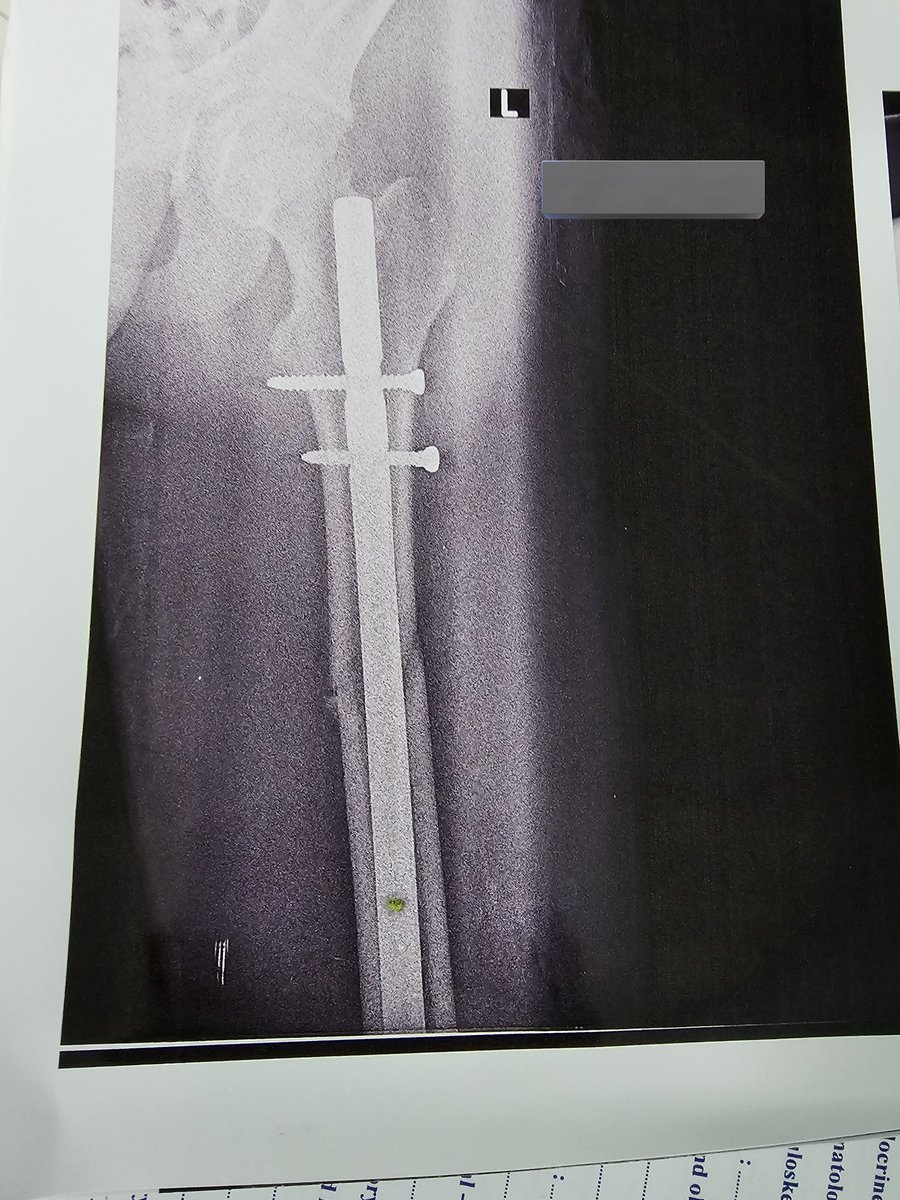

I’m bionic for real now 🦾